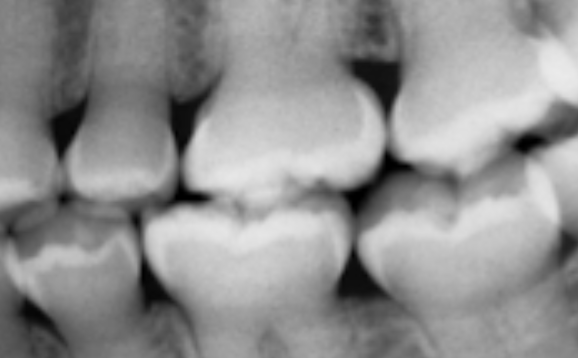

A mother brought in a child with confronts that their teeth appear to be “wearing away.” An X-ray was taken revealing the following. What is the likely cause?

A

Dentogenesis imperfecta (bc you cannot see the pulp chambers)